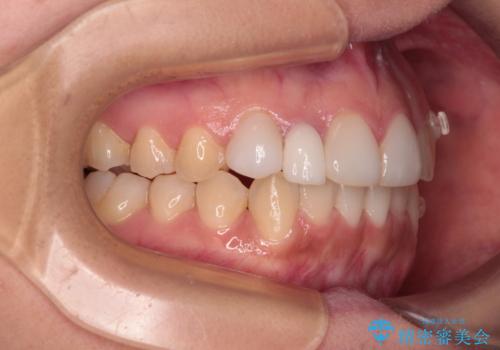

前歯のデコボコが気になる インビザラインによる矯正治療

- 上下前歯のデコボコを気にして来院された患者様です。

インビザラインによる上下歯列の拡大と、IPR(歯と歯の間を削る)にるスペースの獲得により、前歯のデコボコを改善することとしました。